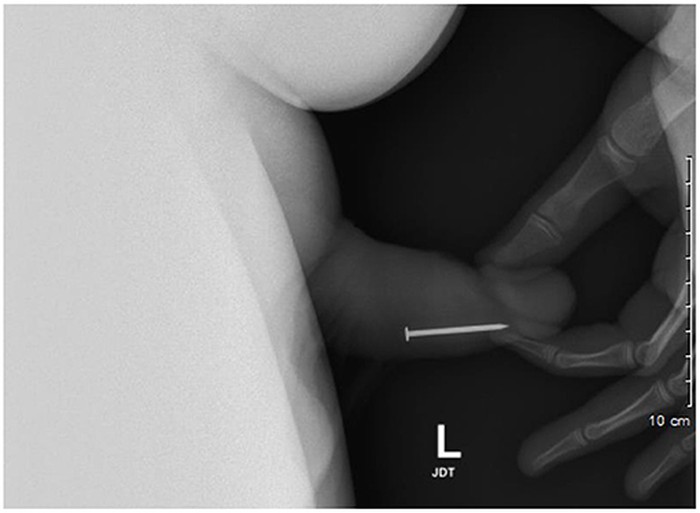

Jakarta - Seorang remaja laki-laki berusia 17 tahun memiliki riwayat memasukkan benda ke dalam uretranya sendiri berkali-kali. Mulai dari paku hingga sekrup.

4 Foto Mr P Remaja 17 Tahun Berkali-kali Kemasukan Benda Asing